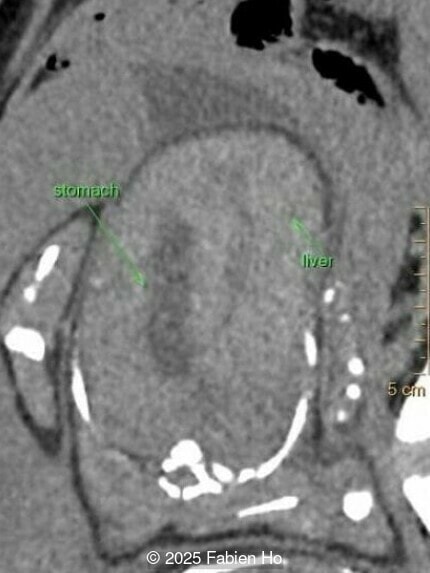

Coronal image of the thorax and abdomen

Image 5 Coronal image of the thorax and abdomen

Axial image of the abdomen

Image 7 Axial image of the abdomen

Our prenatal ultrasound revealed a male fetus with megabladder, dilation of both ureter and kidneys, and thinned kidney parenchyma consistent with Lower Urinary Tract Obstruction (LUTO).  Additional findings suspected on ultrasound and confirmed on computed tomography included:

• Short long bones (<1st percentile), normal mineralization, and no sign of lethal chondrodysplasia

• Evidence of Potter's sequence due to the lower urinary tract obstruction with small thorax compared to the abdomen, hyperextended neck, and pes varus.